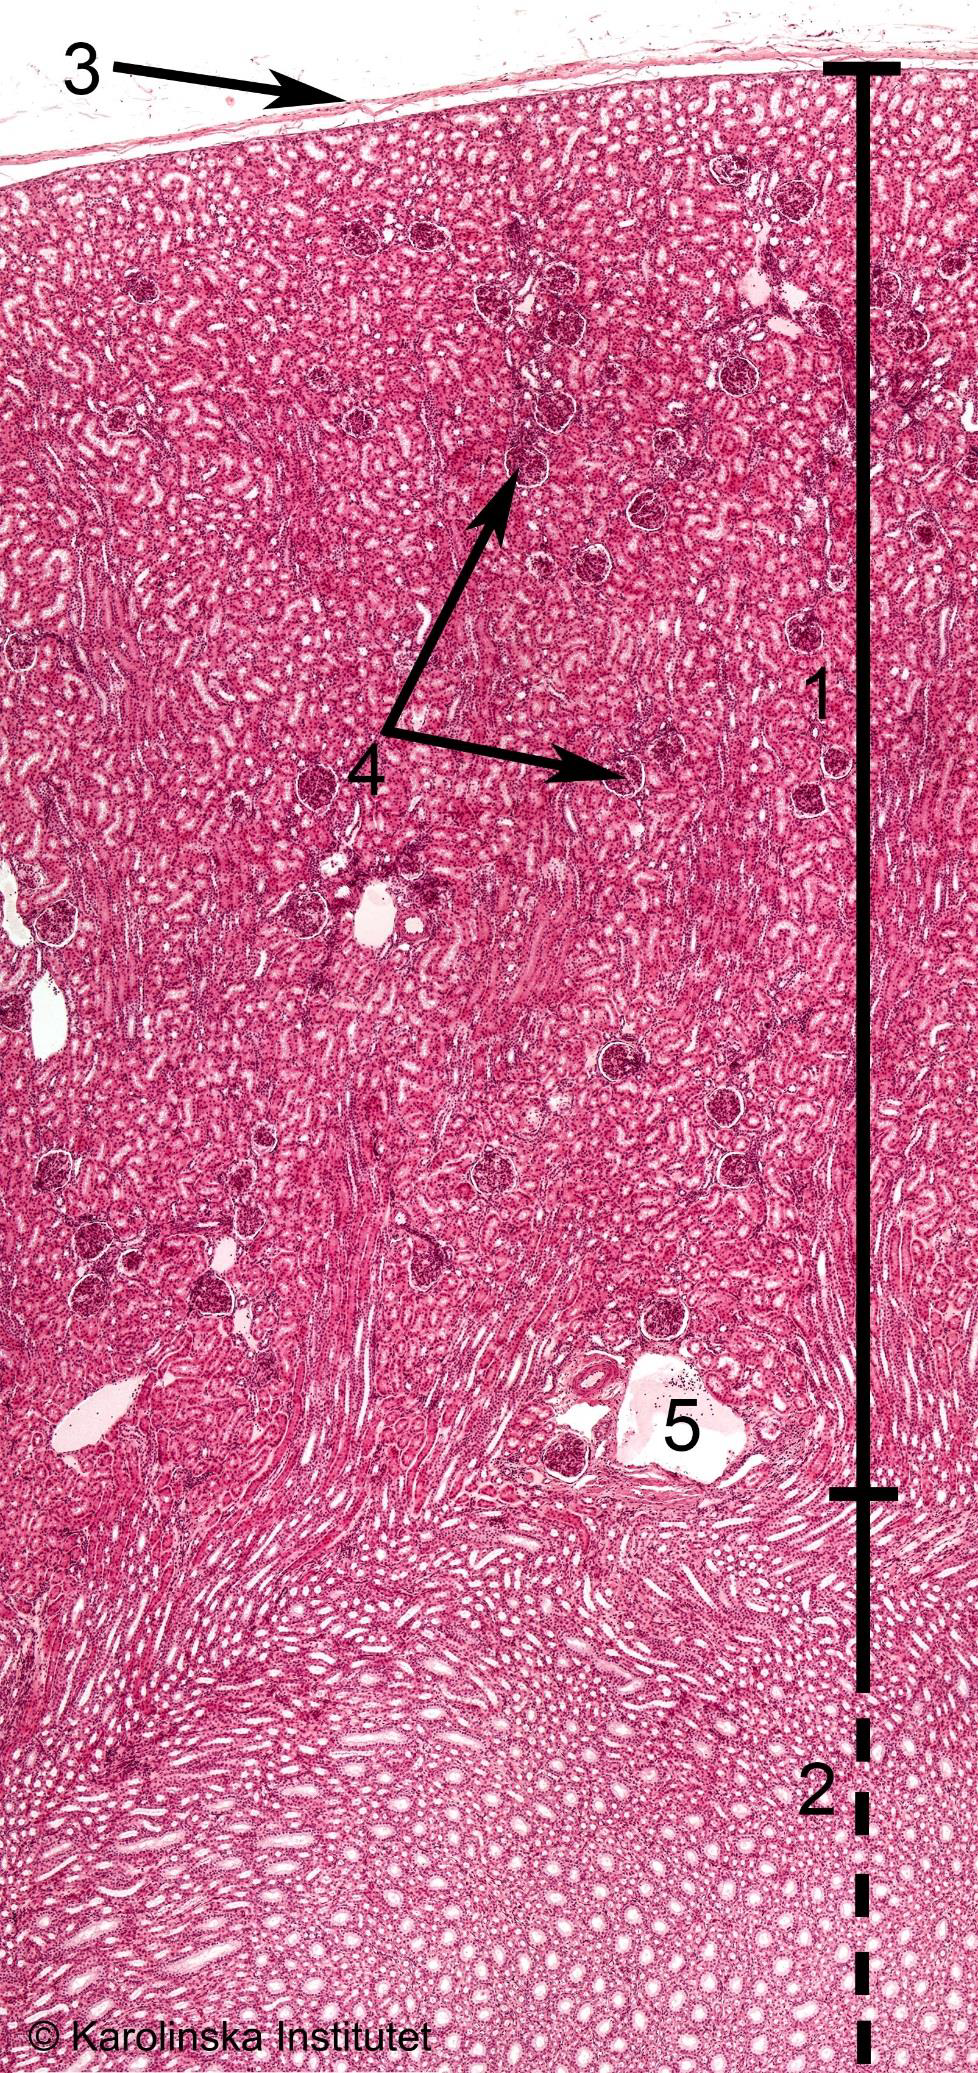

8. AlveoliKidney

1

2

3

41. Cortex,

2. Medulla,

3. Capsula,

4. Glomeruli

2. Bowman’s capsule